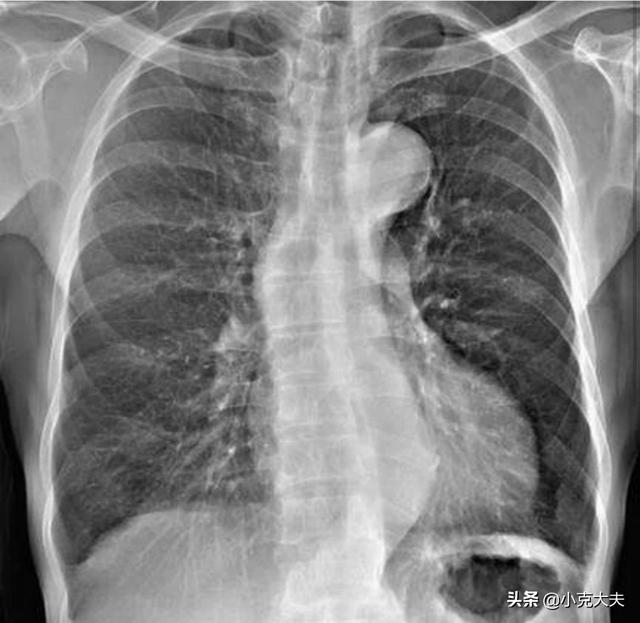

Tout d'abord, les poumons sont le principal lieu d'échange de sang et de gaz dans le corps humain, leur fonction est donc très puissante, mais le tabagisme prolongé, la pollution atmosphérique, l'hérédité et d'autres facteurs entraînent de plus en plus de lésions pulmonaires, dont les plus courantes sont la bronchopneumonie, l'emphysème, la tuberculose, le cancer du poumon et d'autres lésions, mais le cancer du poumon étant le plus grave, certains des symptômes sont encore très évidents lorsque les lésions pulmonaires se manifestent.

1. Cyanose du lit du clou, principalement observée chez les patients présentant des lésions pulmonaires graves, principalement en raison de lésions pulmonaires, d'un dysfonctionnement pulmonaire, d'une ventilation et d'une hyperventilation anormales, de lésions pulmonaires ne permettant pas d'utiliser complètement l'oxygène, telles que la bronchite mantellique, l'emphysème, l'œdème pulmonaire, etc.

2. Outre la cyanose du lit de l'ongle, certains patients souffrant d'une maladie pulmonaire chronique peuvent également présenter un doigt en forme de pilon, également appelé doigt en forme de pilon, principalement en raison d'une maladie pulmonaire, causée par une hypoxie chronique à l'extrémité du doigt, un empoisonnement, etc., le flux sanguin est relativement riche dans les tissus mous en raison de l'expansion des capillaires et de l'émergence d'une hyperplasie, d'une hypertrophie, d'un élargissement, la manifestation de la racine de l'ongle de l'extrémité du doigt à l'extrémité de l'arc bombé, qui peut être vu dans une partie de l'abcès pulmonaire, la dilatation des bronches, une partie du cancer du poumon. Les patients présentant un doigt inexpliqué en forme de pilon comme première manifestation. Certains patients peuvent également présenter des douleurs inexpliquées dans les articulations des doigts.

Les maladies pulmonaires ont également une incidence élevée, alors pour la santé des poumons, le problème le plus courant est la toux, mais en plus de la toux, dans la lésion supérieure apparaîtra également certains changements, tels que les changements les plus typiques est le doigt de pilon, c'est-à-dire, l'extrémité du pouce hypertrophie, la racine du rétrécissement, c'est-à-dire, le gaz pulmonaire est insuffisant, facile à souffrir de maladies respiratoires. Bien sûr, en plus de ce symptôme sur le doigt, les poumons, s'il y a une lésion, auront également une toux grave, les expectorations auront une mousse rose, des difficultés respiratoires, une toux grave apparaîtra également pour cracher du sang.